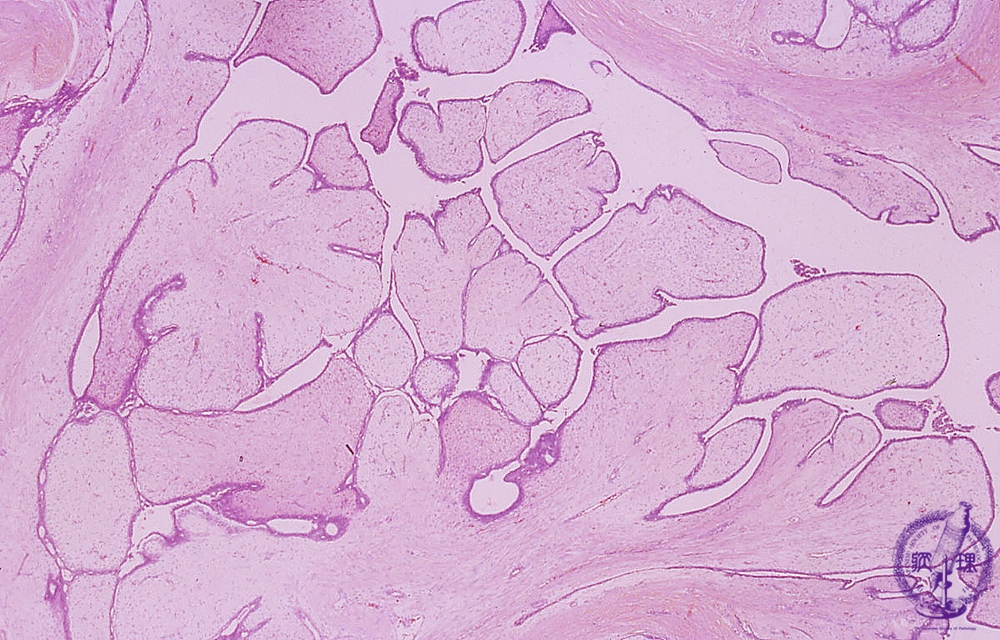

Microscopic image(HE stain, low power view):Both proliferating epithelial and stromal cells form leaf like structures. Proliferative stroma associated with edematous changes.